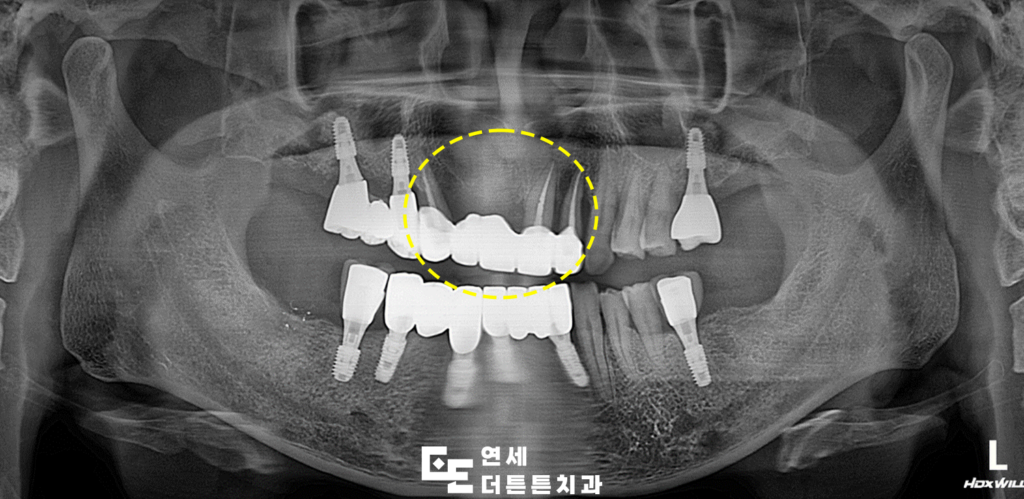

오늘은 염증이 심한 앞니 브릿지를 제거하고

수락산역치과 앞니임플란트를 진행하신 환자분을

소개해 드리도록 하겠습니다.

환자분께서는 오래전 씌웠던 앞니 브릿지가

흔들리는 느낌이 드신다며 내원해 주셨습니다.

겉으로 보기에는 문제가 없는 듯 보였으나

파노라마를 촬영해 보니, 지탱하고 있던 양쪽

지대치 뿌리 쪽 염증으로 인해 잇몸뼈가 거의

남아 있지 않을 만큼 녹아 있었고

살려 쓰기에는 무리가 있다고 판단되어

발치 후 임플란트 식립 계획을 수립하였습니다.